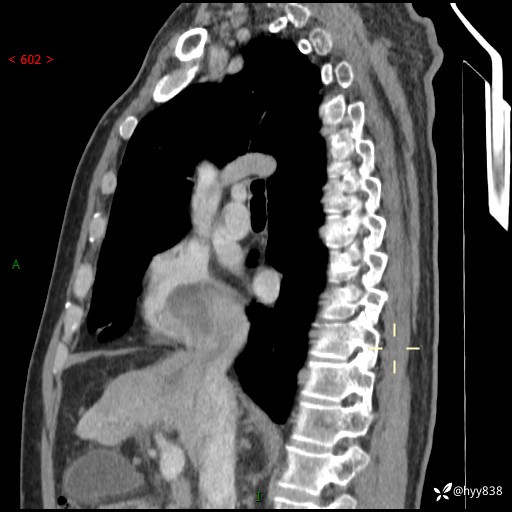

现病史:患者一周余前因腹胀就诊我院消化科门诊,查心脏彩超提示右房内异常回声(粘液瘤?),无明显心慌、气喘、胸闷,无明显胸痛、咳嗽咳痰等不适,活动量增加后出现心慌、气喘不适。现为求进一步治疗,就诊我科,门诊遂以“心脏肿物”收入院。 自发病以来,精神睡眠一般,食欲尚可,大小便正常,体力下降,体重无明显变化。

胸部CT平扫+增强